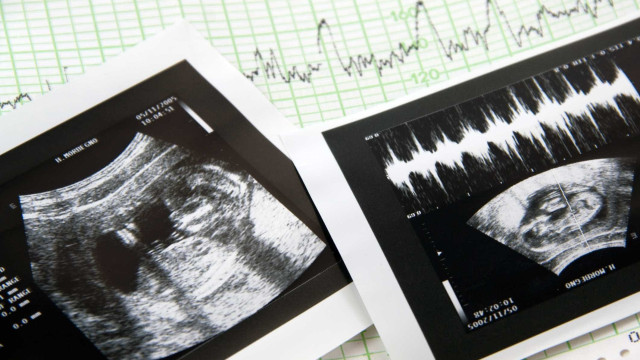

O caso remonta a 2023, quando uma família viu nascer um bebé com uma perna incompleta e apenas dois dedos num dos pés. A clínica agora visada num processo da IGAS, e já sobre investigação na Justiça, não detetou a malformação durante a ecografia morfológica.

A Inspeção-Geral das Atividades em Saúde (IGAS) abriu um processo de fiscalização à clínica Ceraque, em Pinhal Novo, que não terá detetado uma malformação grave num feto, durante a ecografia morfológica (que permite ver a anatomia do bebé).

Durante toda a gravidez, assim como na ecografia morfológica - feita nesta clínica - foi dito aos progenitores que o filho não tinha nenhum problema. Foi só no nascimento da criança, que os pais descobriram que o bebé tinha a perna direita incompleta e apenas dois dedos no pé.